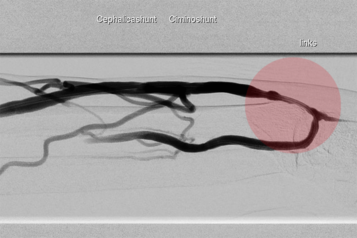

Patienten die sich einer regelmäßigen Blutwäsche unterziehen müssen (Dialyse), haben dafür einen operativ geschaffenen Gefäßzugang zum Punktieren (Dialysefistel/Dialyseshunt). Dazu wird eine Hautvene direkt an eine Arterie angeschlossen. In dieser Shuntvene können Einengungen und Verschlüsse auftreten, die mit vielen interventionellen Methoden behandelbar sind. Diese Behandlungen führen wir über einen Zugang in der Shuntvene meist ambulant in Zusammenarbeit mit der jeweiligen Dialyseeinrichtung durch.